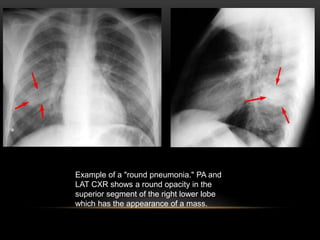

Example of a "round pneumonia." PA and

LAT CXR shows a round opacity in the

superior segment of the right lower lobe

which has the appearance of a mass.